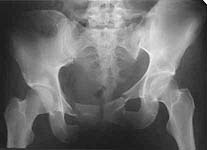

An example of closed ex-fix applcation in a similar case (pelcvic injury with posterior lesion) is attached. I put only AP views to decrease size of the posting.

if these xrays are all from the same case this is a very nice reduction. I would like to see the three views of the pelvis pre and post as well as the ct. kellam study showed 27% of unstable pelvis fractures maintained their reduction with an external fixation. Additionally, this case is through the si joint instead of the crescent fracture that was presented. These behave differently.